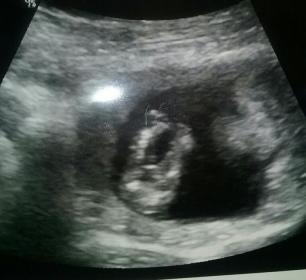

Attachment 33110

Here's another shot

A better pic...Attachment 33111

Attachment 33112

I didn't get any nub shots.. wish I had

That last pic looks like a boy to me :) I don't think that is a cord...

Looks like a boy :)

I say boy too. [emoji170]